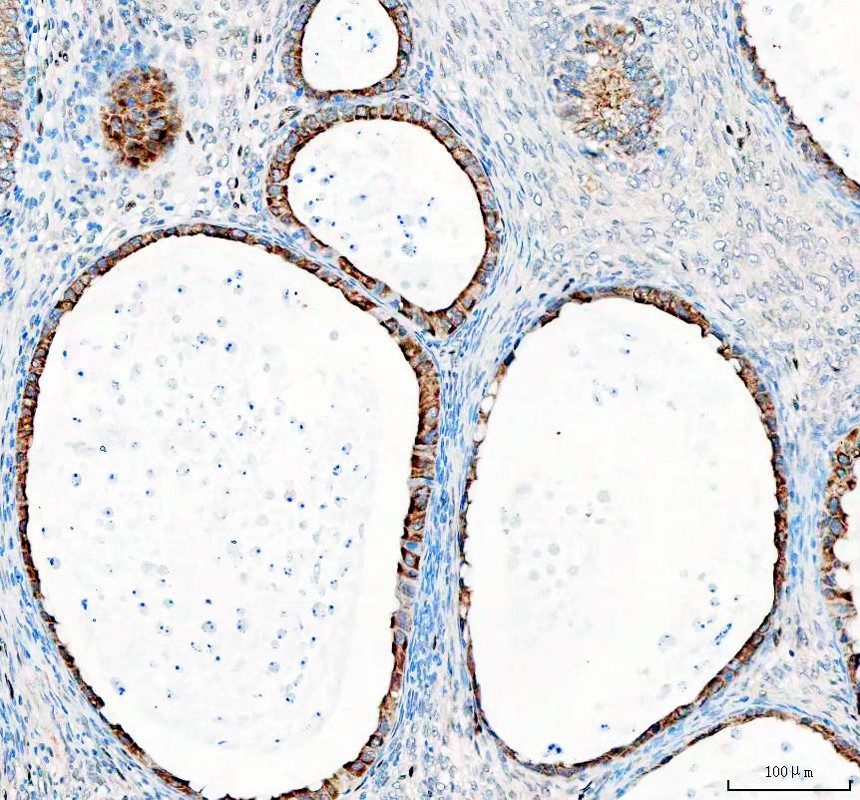

IHC analysis of GSK3B using anti-GSK3B antibody (A00791-3) .

GSK3B was detected in a paraffin-embedded section of human ovarian cancer tissue. The tissue section was incubated with rabbit anti-GSK3B Antibody (A00791-3) at a dilution of 1:200 and developed using HRP Conjugated Rabbit IgG Super Vision Assay Kit (Catalog # SV0002) with DAB (Catalog # AR1027) as the chromogen.

IHC analysis of GSK3B using anti-GSK3B antibody (A00791-3) .

GSK3B was detected in a paraffin-embedded section of human ovarian cancer tissue. The tissue section was incubated with rabbit anti-GSK3B Antibody (A00791-3) at a dilution of 1:200 and developed using HRP Conjugated Rabbit IgG Super Vision Assay Kit (Catalog # SV0002) with DAB (Catalog # AR1027) as the chromogen.